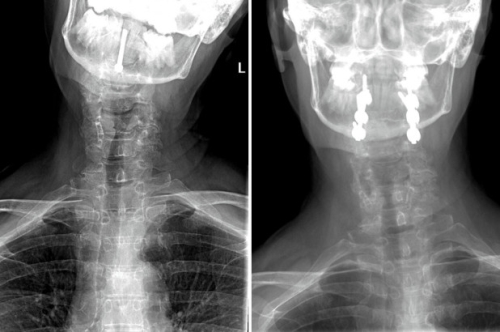

Dr. Richard Lee took over her care after a previous operation to fix her neck fracture with a singular vertebral screw had failed. Ruth’s neck injury had healed in a tilted/slanted position because her C1 ring had flipped horizontally and was resting on her C2 vertebrae. This was preventing her from turning her head from side-to-side without being in excruciating pain. She had been living w/ excruciating daily pain and with every move she risk of becoming paralyzed.

Photo Caption: Before and After X-rays of Ruth Bobeczko neck. The image on the left shows her crooked posture on the left. The image to the right is after Dr. Lee performed neck revision surgery.